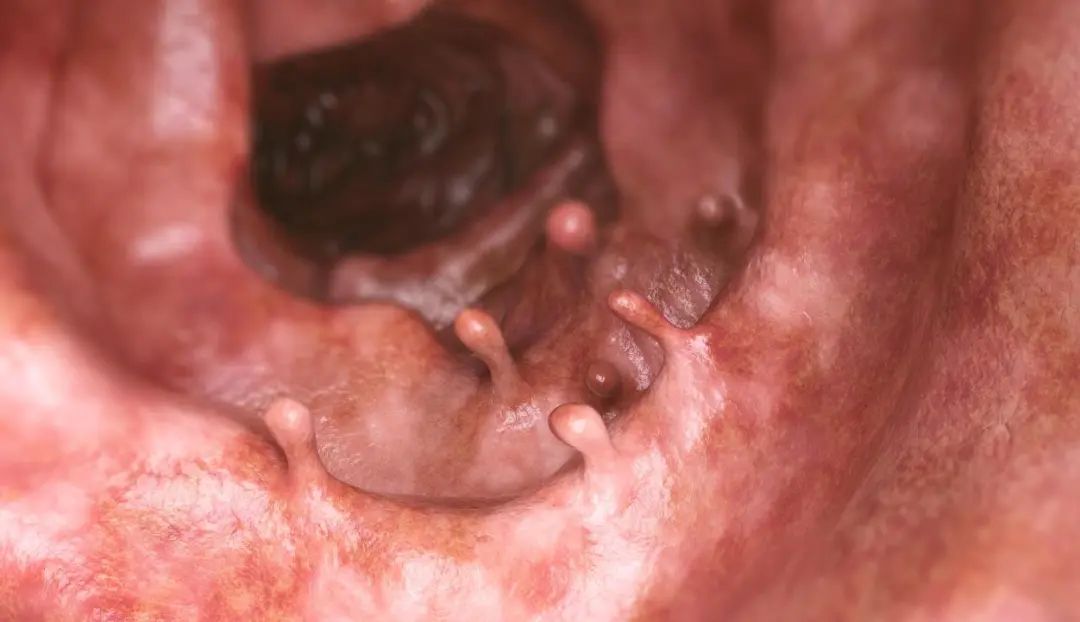

大肠是结肠(包括盲肠和阑尾)、直肠和肛管的统称,位于消化道的末端。医学上,将 发生于大肠的恶性肿瘤称为大肠癌。

根据不同的分类方式,大肠癌可分为不同的类型。以肿瘤 发生的部位 分类,大肠癌可分为:阑尾癌、盲肠癌、升结肠癌、横结肠癌、降结肠癌、乙状结肠癌、直肠癌以及肛管癌;以肿瘤的 大体形态 分类,大肠癌可分为:隆起型、溃疡型和浸润型;以肿瘤的 组织学类型 分类,大肠癌可分为腺癌、特殊类型的腺癌、鳞癌、未分化癌等。根据 是否有家族史 分类,大肠癌可分为遗传性大肠癌和散发性大肠癌。大肠癌的发病率仍然呈现逐年增加的趋势。根据2020年的全球癌症数据报道,大肠癌为世界第三高发的恶性肿瘤。 在中国,大肠癌为第二高发的恶性肿瘤, 2020年全年新发病例数高达55.5万 [1] ,给国民健康和经济带来了沉重的负担。1962年,上海市刚刚开展流行病学调查时,大肠癌的年发病率约为8.7/10万, 到2015年,上海市的大肠癌年发病率达到了65/10万,增长了7倍多。

即针对大肠癌的 病因 进行预防。首先, 合理、均衡的饮食非常重要。 前文已经提及,摄入高蛋白、高脂肪和低纤维素的食物是大肠癌发病的危险因素,因此避免高蛋白、高脂肪的摄入,增加富含纤维素的食物摄入可以在一定程度上预防大肠癌的发生。此外,大肠癌的发生发展需要经历漫长的过程。大肠癌一般由大肠息肉及腺瘤演变而来,对于非遗传性大肠癌,此演变过程至少需要5年时间,而对于遗传性肠癌,通常也需要1-3年的演变时间。因此,在大肠息肉/腺瘤演变至大肠癌的过程中, 若能够及时发现并处理掉大肠息肉/腺瘤,也可以预防大肠癌的发生。